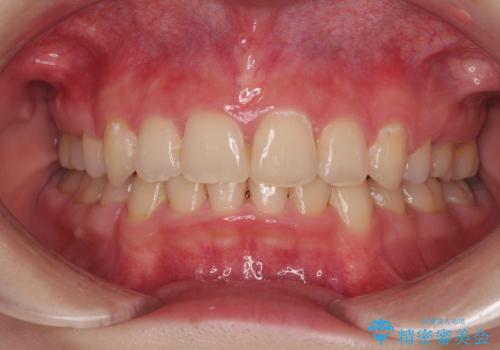

色のバランスの悪い前歯 オールセラミッククラウンで自然な口元に